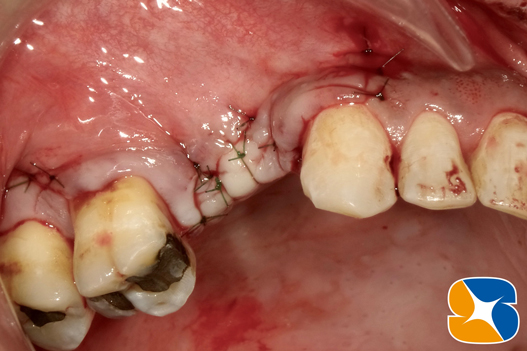

人工骨とご自身のアゴ骨の移植が完了しました。

フィブリンゲル膜で移植患部を保護します。

傷口を縫い合わせたところです。再生治療付きの骨造成を行いましたので、6ヶ月もあれば通常の骨に生まれ変わります。